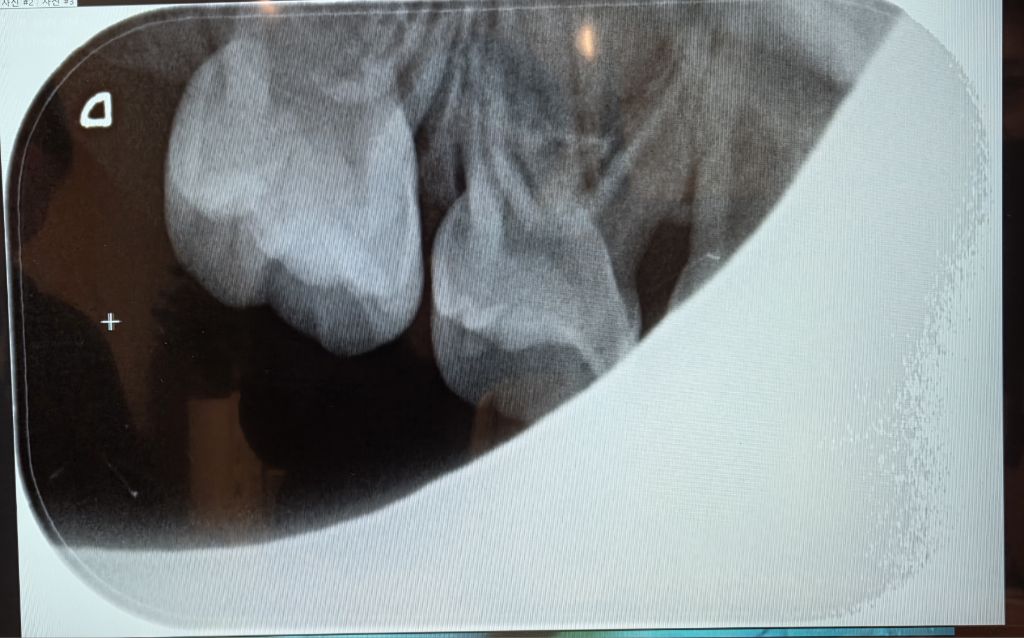

아이가 너무 어려서 최대한 치료를 늦추고 싶은데요, 이 상태로 더 악화되지 않고 최소 6개월 버틸 수 있을까요?

아이가 자라는 동안 신경치료는 최대한 안 하게 하고 싶은데요, 그러기 위해서는 치료 방향을 어떻게 잡는 게 좋을까요? 지금 당장 때울 곳들 때우는 게 나을까요? 아니면 그래도 6개월 정도나 그 이상 버텨 보아도 괜찮을까요?

집에서 식생활, 양치질 관리하면서 버티다가

구멍이 커지면

1개씩 레진/ GI 또는

아프면 신경치료 +크라운

이런 방식을 권하고 싶습니다만

현실적으로 그렇게 해 주는 치과가 없다는 점이 난관이지요.